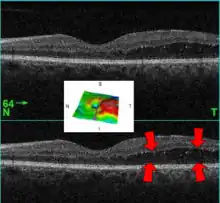

A 61-year-old man with medical history of type 2 diabetes that presents a macular edema, evidenced by an OCT (the edema marked with arrows). The central image is a 3D reconstruction of the retinal thickness (the edema is coloured in red).